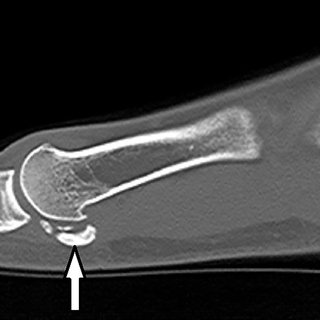

• Sclérose et petits fragments

du abasculaire avasculaire os sésamoïde sesamoide sesamoïde sésamoide